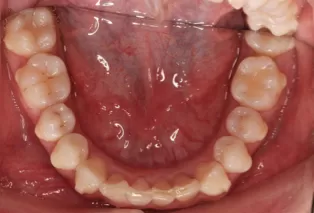

Intraoral photos after treatment